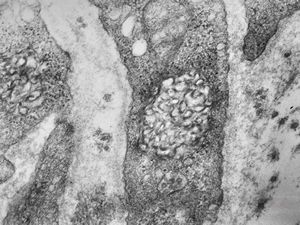

F, 46y. | verruca vulgaris … intranuclear virions

F, 46y. | verruca vulgaris … intranuclear virions

F, 46y. | verruca vulgaris … intranuclear virions